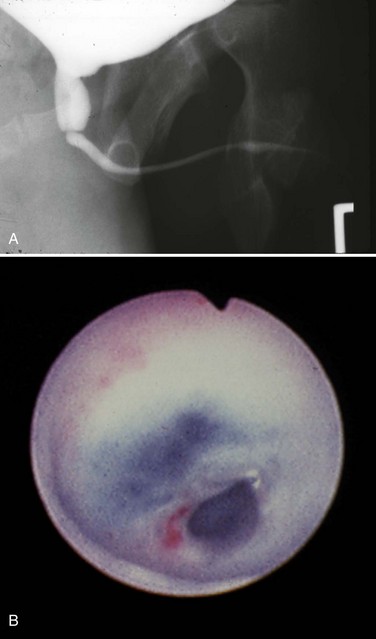

High voiding pressures distend and thin the prostatic urethra. The storage capacity of the prostatic urethra sometimes exceeds that of the bladder because of the relative lack of muscle there. The verumontanum is distorted, and the ejaculatory ducts may be dilated from refluxing urine. The bladder neck is rigid and hypertrophied (Fig. 126–4). This high bladder neck was once mistaken as another cause of obstruction and was surgically incised to facilitate bladder emptying. Unfortunately, this practice often resulted in total incontinence. Today it is understood that the appearance of the bladder neck is a result of distal obstruction and not obstructive lesion itself. Bladder neck appearance and function usually improves after the obstructive valves are destroyed.

Figure 126–4 A, Voiding cystourethrogram shows a posterior bladder diverticulum near the base of the bladder and an extremely high bladder neck. A catheter passed blindly can fail to pass over the bladder neck and coil in the dilated posterior urethra. B, Massive vesicoureteral reflux in a boy with valves.